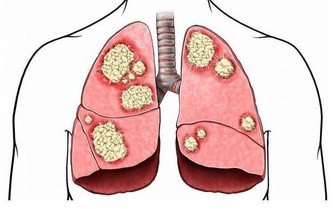

3. 你的腸道裡有寄生蟲

大便中的白色斑點也可能是絛蟲或蟯蟲。雖然如今絛蟲感染並不常見,但依然有可能。如果看到白色或黃色的斑點,可能就是絛蟲,它們通常是扁平的、方形的,大小與米粒相當。有些人可能沒有症狀,但有些人可能出現胃痛或腹瀉。人們通常是因為吃生的或未煮熟的肉而感染絛蟲。絛蟲感染比較好治療,一粒藥丸就足以殺死絛蟲,它會從糞便中排出體外。